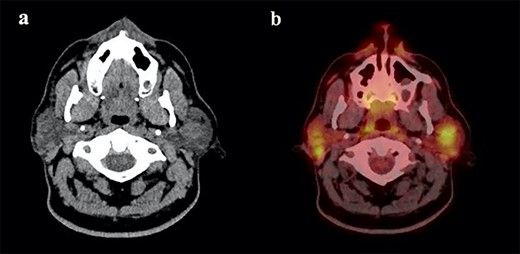

(a) Maxillofacial Axial CT with contrast showing multiple bilateral parotid gland lesions demonstrating internal enhancing septations with the largest lesion located in right parotid tail, measuring 1.9 x 2.1 cm and (b) associated PET CT scan showing bilateral hypermetabolic parotid lesions measuring up to a maximum standardized uptake value (SUV) of 10.0 on the left and 9.0 on the right.

The patient presented 6 months later with progressive bilateral cheek swelling, more significant on the right side. Repeat CT revealed multiple bilateral parotid gland lesions with the largest located within the right parotid tail (Fig. 2a). Positron emission tomography (PET) scan was ordered to rule out other diagnostic considerations including primary parotid tumors such as Warthin’s tumor or non-Hodgkin lymphoma, or secondary malignancy. Bilateral hypermetabolic parotid lesions were identified along with diffuse bilateral cervical adenopathy (Fig. 2b). Findings suggested bilateral BLEC which raised suspicion for a potential immunosuppressive state. An HIV panel was performed with a positive result. The patient underwent initial local aspiration and drainage to palliate his symptoms of cheek discomfort and treatment for HIV was discussed. Patient has since been placed on HIV medication for management and his bilateral cysts and lymph nodes have reduced in size at follow-up visits with no signs of further recurrence.